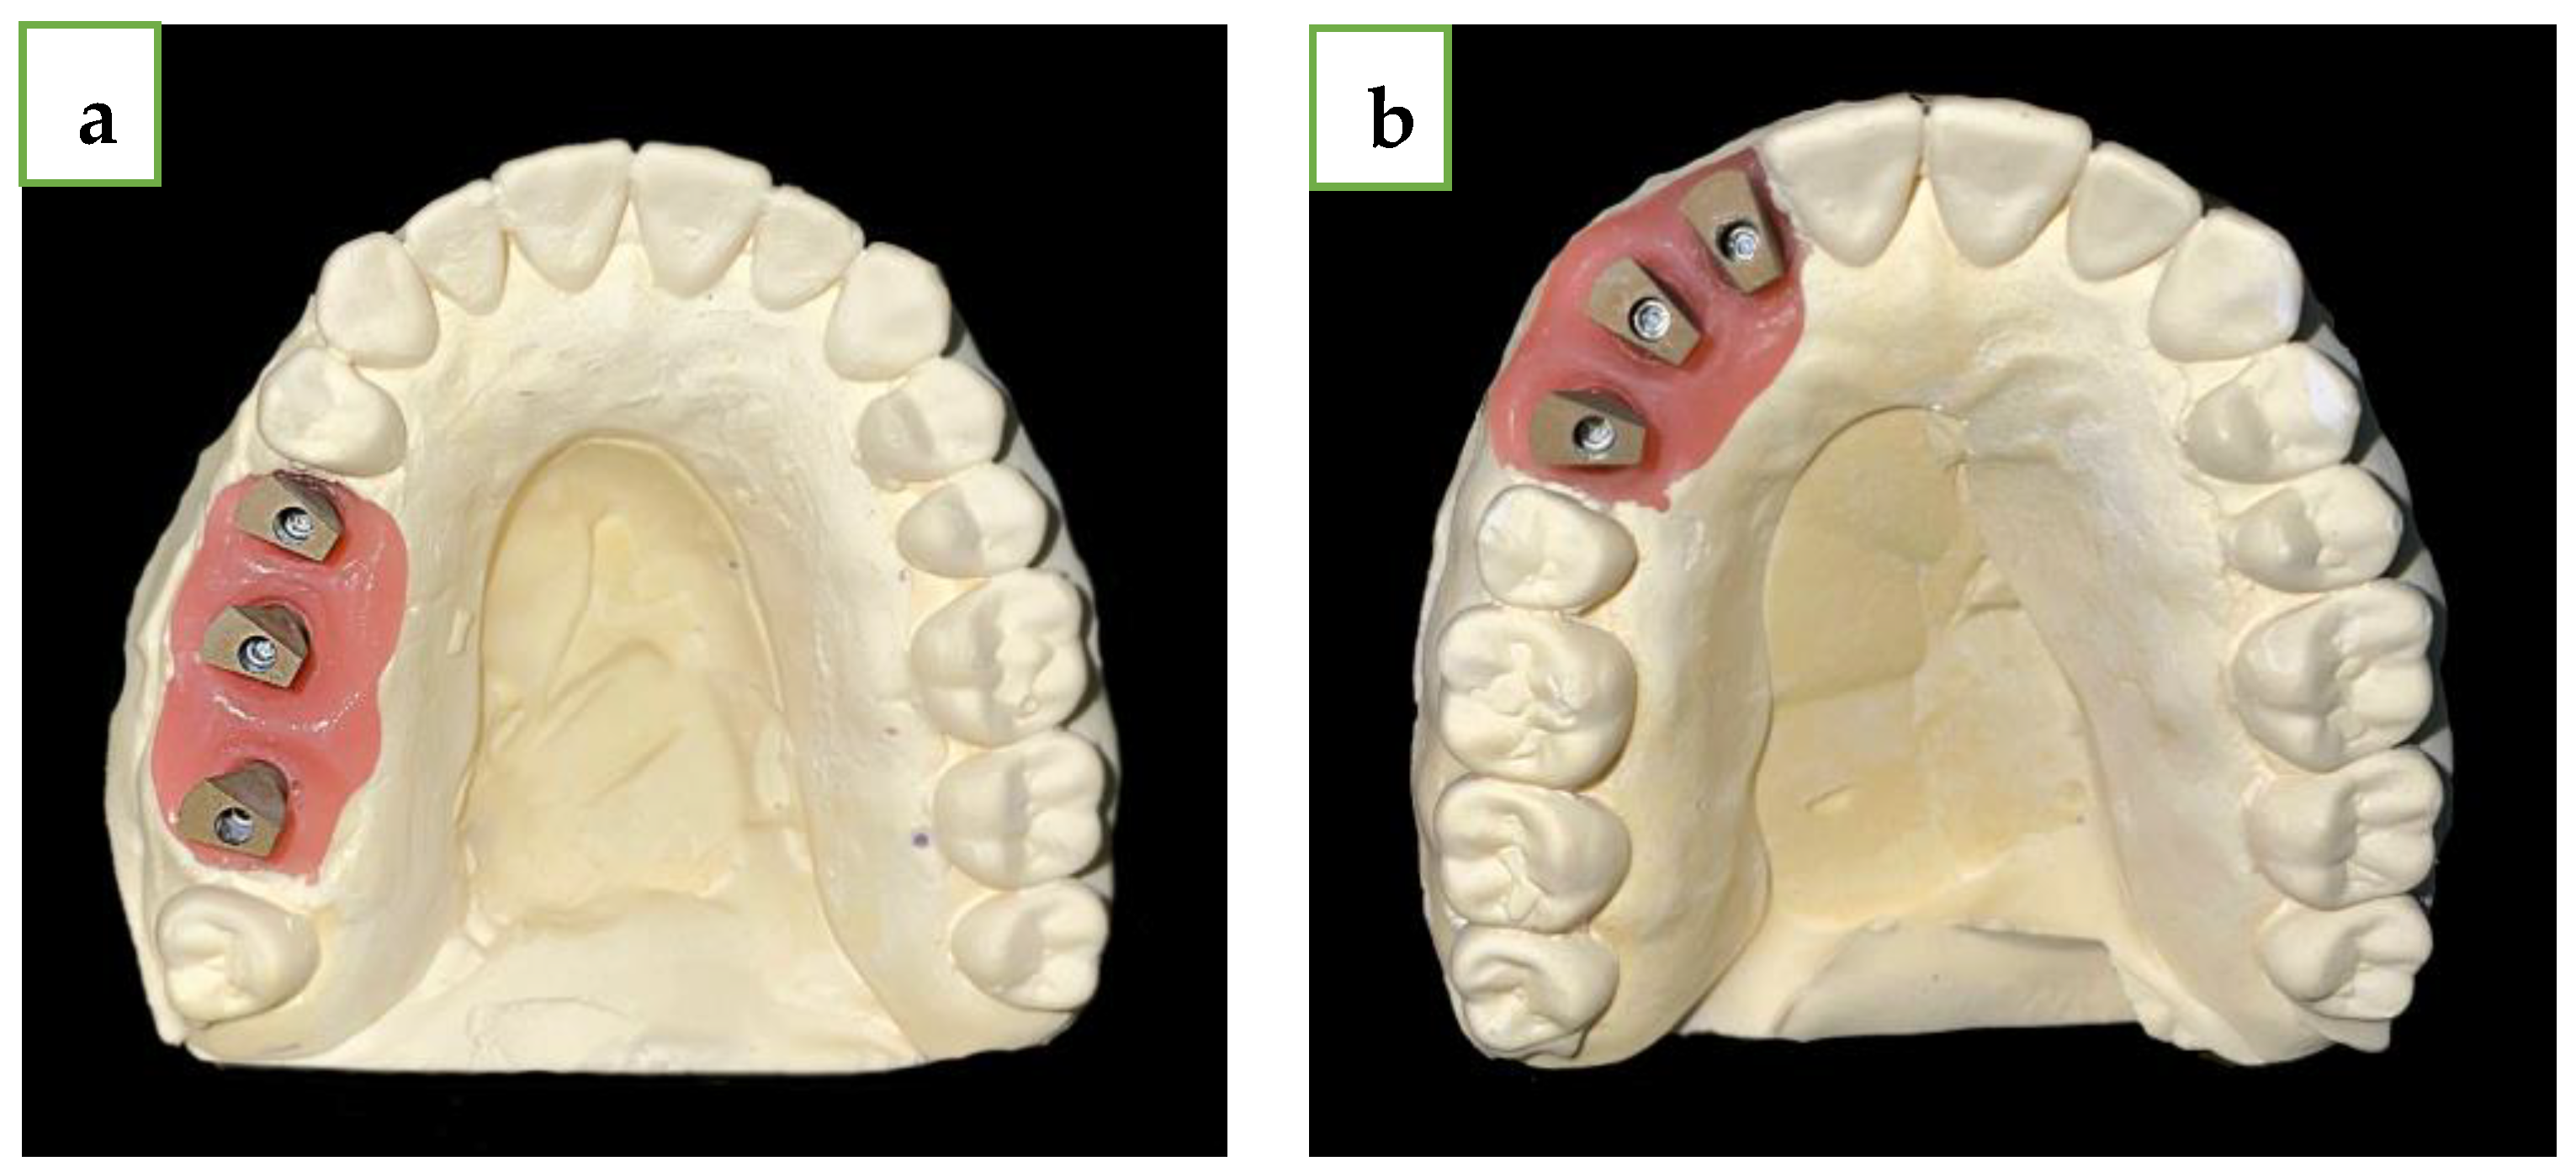

2. Materials and Methods